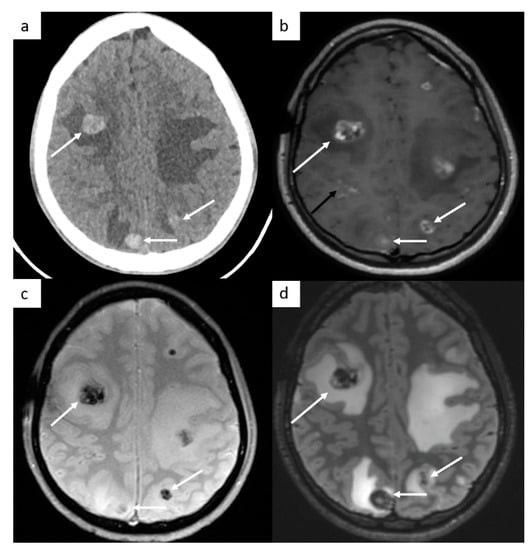

Brain imaging is not routinely performed but is indicated in symptomatic patients, in patients with high risk factors such as choriocarcinoma type tumor (likely hemorrhagic metastases), serum marker HCG > 10,000, or in advanced metastatic disease, including supradiaphragmatic nodal disease (Figure 3).

Figure 3.

Brain metastases. Cerebral CT brain demonstrates several hemorrhagic metastases (a). MRI confirms the presence of several metastases with peripheral enhancement ((b), white arrows). They are hypointense on SWI-weighted images (c), with surrounding edema (d) on FLAIR-weighted images. In this case, a leptomeningitis is associated ((b), black arrow).